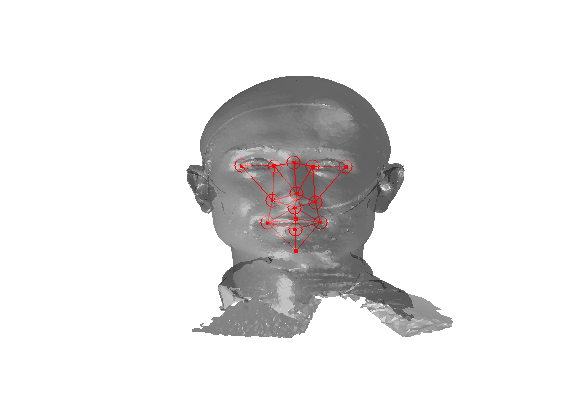

Referring to Fig. 5, our method is a supervised learning technique - landmarks are marked by hand on a set of training images. We used 279 faces (each different individuals) in the Face Recognition Grand Challenge (FRGC) dataset [26]. The landmarks used are described in table 1 111Some descriptions taken from www.facebase.org and can be seen on an example FRGC 3D face scan in Fig. 7.

Fig. 9 shows examples of the fitted model (trained on FRGC data) on the first four subjects in our Headspace training set. Note that the mean of the landmarks in the sparse model is centred on the orgin, and so the scan data is moved towards that and becomes frontal in pose. We note that other researchers [28] have used 3D landmark localisation to find the head, but often this only includes landmarks that are relatively easy to localise, namely inner eye corners and nose. Localising more landmarks over a wider facial area has a number of advantage in terms of cropping, pose normalisation and global 3D template warping, all of which are described later.